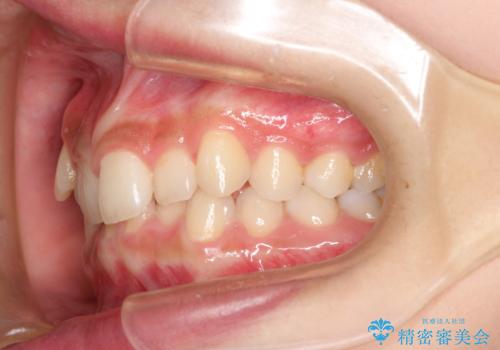

インビザラインを使用した深いかみ合わせの矯正

- 前歯のガタガタを主訴に来院された患者様です。

八重歯になっており、下顎の前歯が上顎の前歯に隠れてしまう、ディープバイトという状態でした。

インビザラインを使用して矯正する計画としました。